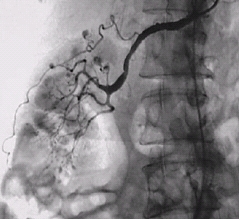

급성 관동맥 증후군(Acute Coronary Syndrome)

협심증

죽상경화증

급성 심근경색증

불안정형 협심증

심장내과

심장혈관흉부외과

급성 심근경색증(Acute myocardial infarction)

허혈성 심질환

심장병원